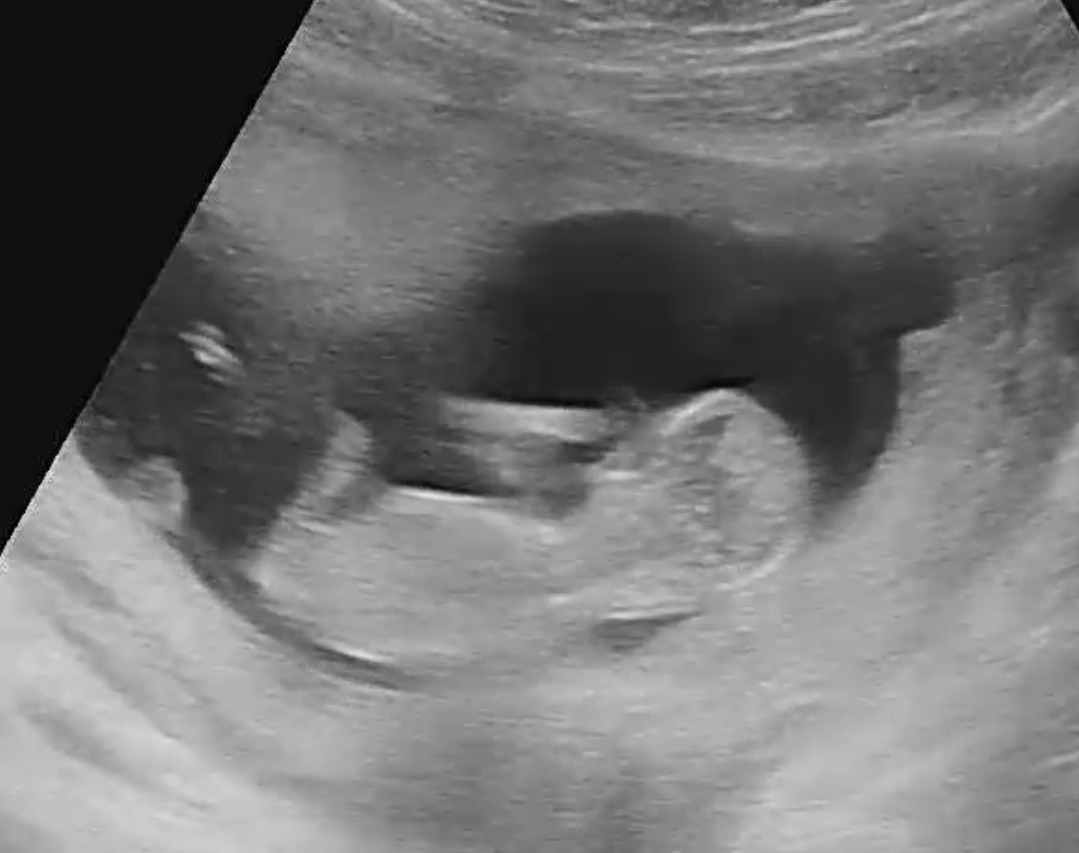

초음파로 보는 너는 이미 한 명의 사람 모양을 하고 발을 구르고 손가락을 꼼지락 하는데 그 움직임이 하나도 느껴지 않으니 답답할 나름일밖에...

9시가 넘어 의사가 출근하고 초음파로 네 모습까지 확인하고 나서야 집으로 돌아올 수 있었지.